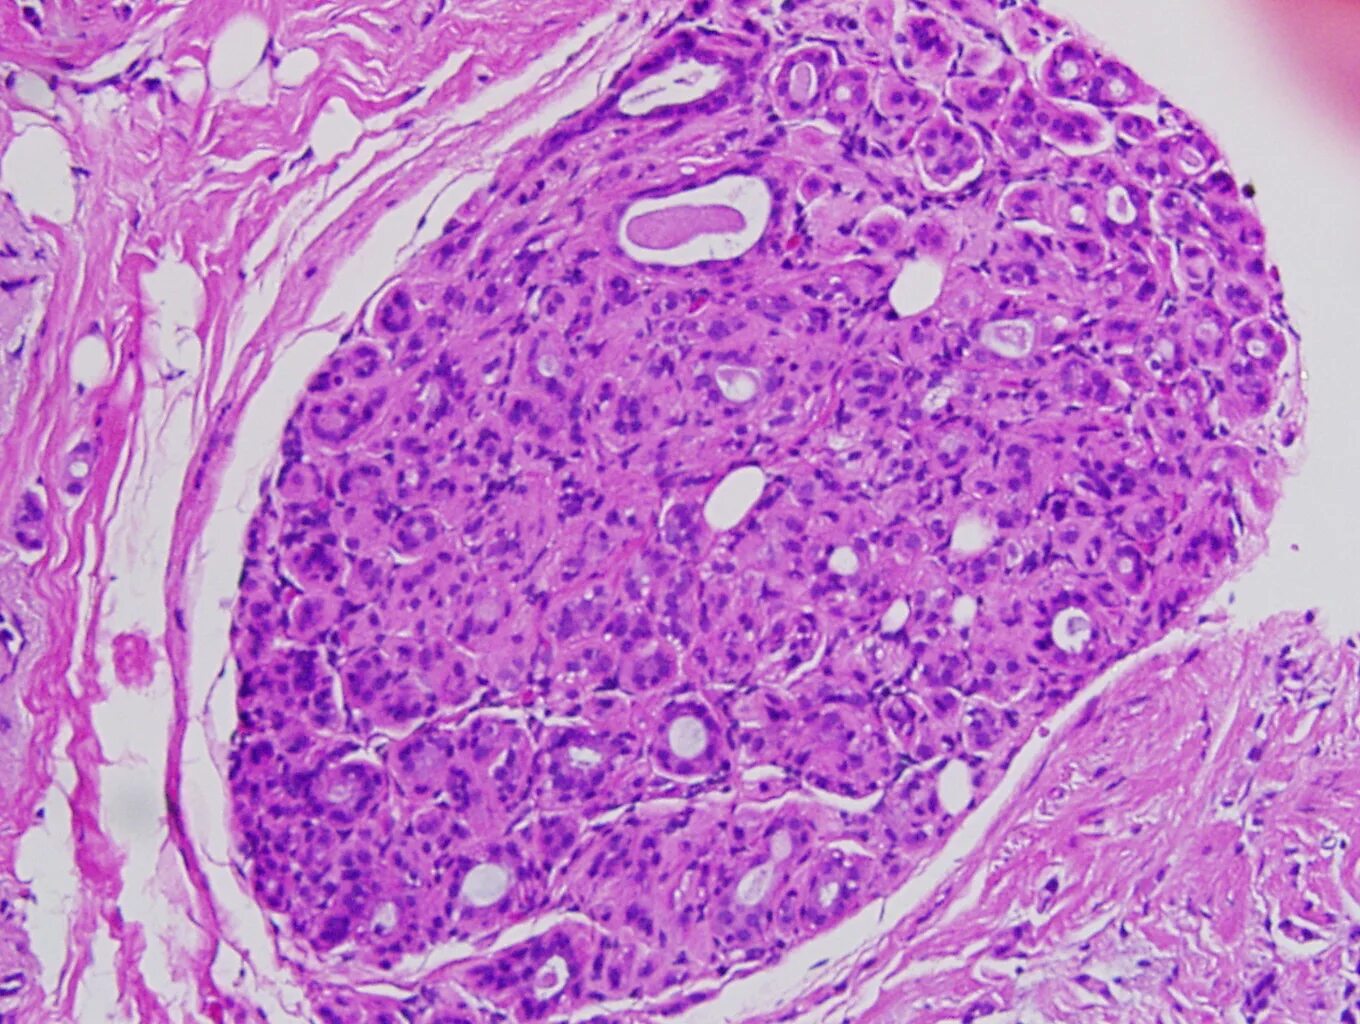

Протоковая карцинома молочной железы гистология. протоковая карцинома молочной железы микропрепарат. внутрипротоковая карцинома молочной железы гистология. внутрипротоковая карцинома молочной железы микропрепарат.

Внутрипротоковая карцинома молочной железы микропрепарат. внутрипротоковая карцинома молочной железы гистология. неинфильтрирующий внутрипротоковый карцинома. протоковая карцинома in situ молочной железы.

Внутрипротоковая карцинома. гистологическая классификация опухолей молочной железы. неинфильтрирующий внутрипротоковый карцинома.

Тубулярная карцинома гистология. протоковая карцинома in situ. внутрипротоковая карцинома молочной железы микропрепарат. карциномы in situ молочной железы гистология.

Протоковая карцинома in situ. опухоли молочной железы микропрепарат. протоковая карцинома молочной железы гистология. комедокарцинома гистология.

Инфильтрирующая карцинома молочной железы гистология. внутрипротоковая карцинома молочной железы микропрепарат. внутрипротоковая карцинома молочной железы гистология. комедокарцинома гистология.

Внутрипротоковая карцинома молочной железы гистология. внутрипротоковая карцинома молочной железы микропрепарат. инфильтрирующая карцинома молочной железы гистология. комедокарцинома гистология.